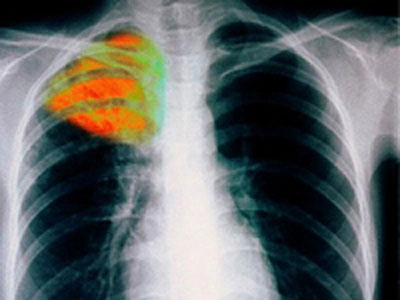

Σοβαρό πρόβλημα Δημόσιας Υγείας, αποτελεί το νέο πρόσωπο της φυματίωσης, η πολυανθεκτική φυματίωση, με τους επιστήμονες να κάνουν λόγο για «ωρολογιακή βόμβα», με προβληματική και ελλιπή αντιμετώπιση.

«Η ασθένεια όχι μόνο δεν έφυγε από τη χώρα μας, παραμένει εδώ και μάλιστα με νέο, πολύ πιο επικίνδυνο, πρόσωπο: την ανθεκτική, την πολυανθεκτική και την εκτεταμένα ανθεκτική φυματίωση. Η έλλειψη διαθέσιμων θεραπειών από τη μία και η λειτουργία μόνο μιας Μονάδας Νοσηλείας ανάλογων περιστατικών, στο Νοσοκομείο “Σωτηρία” από την άλλη, δυσχεραίνουν σημαντικά το έργο των ειδικών επιστημόνων», ανέφερε ο πρόεδρος της Ελληνικής Πνευμονολογικής Εταιρίας Μιχάλης Τουμπής, κατά τη διάρκεια συνέντευξης Τύπου, επ’ ευκαιρία του 23ου Πανελλήνιου Πνευμονολογικού Συνεδρίου, που θα πραγματοποιηθεί στην Αθήνα, από τις 5 έως τις 8 Νοεμβρίου.

Σύμφωνα με τον πρόεδρο της ΕΠΕ, η μονάδα αντιμετώπισης της πολυανθεκτικής φυματίωσης στο νοσοκομείο «Σωτηρία», με 7 κλίνες σε θαλάμους αρνητικής πίεσης, παρακολουθεί φέτος 32 περιστατικά, δύο εκ των οποίων αφορούσαν στην εκτεταμένα ανθεκτική φυματίωση, με το ένα να έχει ήδη καταλήξει.

«Δυστυχώς έχουμε πολλά περιστατικά. Αυτές οι μορφές της φυματίωσης δύσκολα θεραπεύονται, αφενός διότι το μυκοβακτηρίδιο που τις προκαλεί, έχει αναπτύξει αντοχή στα περισσότερα από τα διαθέσιμα φάρμακα, αφετέρου επειδή απουσιάζουν από την Ελλάδα οι εξειδικευμένες υποδομές για την αντιμετώπισή τους», δήλωσε ο κ. Τουμπής και σημείωσε, ότι σε όλη τη χώρα υπάρχει μόνο μία μονάδα αντιμετώπισης της πολυανθεκτικής φυματίωσης, η οποία διαχειρίζεται περί τα 50 περιστατικά ετησίως, ενώ η νοσηλεία και γενικότερα η φροντίδα αυτών των ασθενών κοστίζει από 10 έως 20 φορές περισσότερο από την αντιμετώπιση της κοινής φυματίωσης.

«Αν κάποιος έχει πολυανθεκτική φυματίωση, δεν το γνωρίζει ή το γνωρίζει και κυκλοφορεί ελεύθερα, χωρίς νοσηλευτική φροντίδα, είναι ωρολογιακή βόμβα στα θεμέλια του υγειονομικού συστήματος της χώρας», τόνισε ο κ. Τουμπής, προσθέτοντας, ότι δεν χρειάζεται πανικός, αλλά σωστή ενημέρωση των πολιτών, έγκαιρη διάγνωση και σωστή θεραπεία.